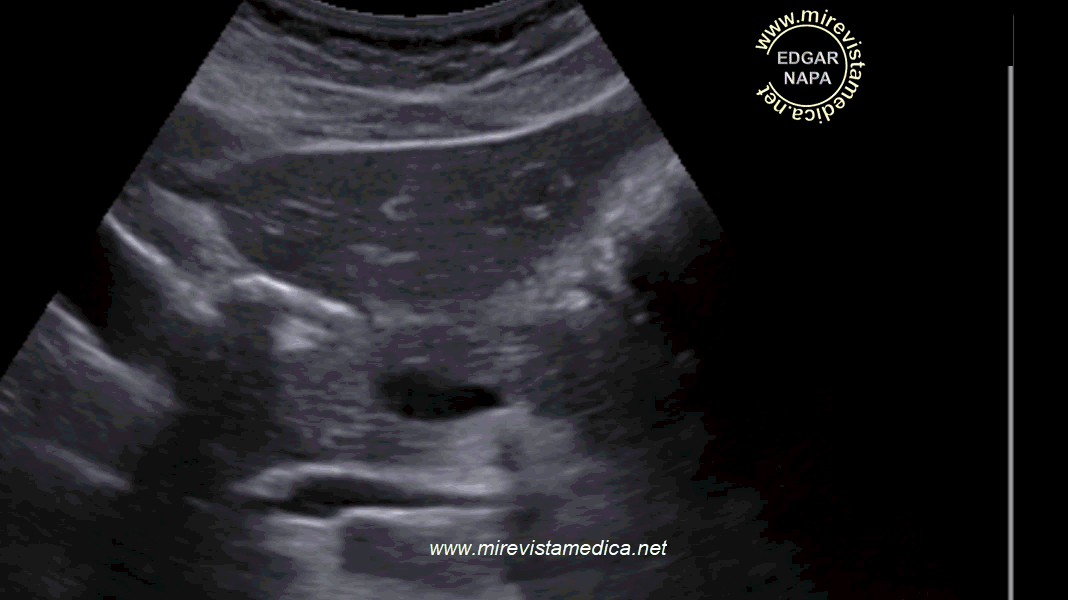

PARTES Y MEDIDAS NORMALES DEL PÁNCREAS EN ULTRASONIDO (incidencia transversa)

1. CABEZA: <30 mm.

2. CUERPO: <25 mm.

3. COLA: <20 mm.

La ecogenicidad del parénquima pancreático varia con edad :

- Es hipoecogénico en pacientes jóvenes.

- Es isoecogénico en pacientes adultos.

- Es hiperecogénico en pacientes adultos mayores.